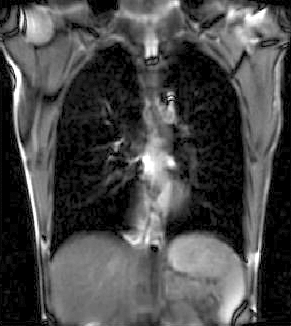

Slicer Registration Library Case #46: 2D Cine MRI of Breathing Cycle

| fixed image/target | moving image |

- reference/fixed : 2D coronal MRI 256x256 , FIESTA sequence ,1.5 x 1.5 x 15mm voxel size

- moving: 2D coronal time series, 200 images total, each as fixed above

Registration Results

| unregistered moving series | moving input after registration (only frames 1-27 shown) | displacements (PDF) |